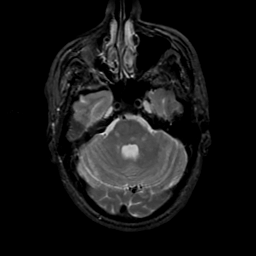

MR Study #17, July 7, 1991 -- Slice #13

[Home][Help][Clinical][Tour 1][Tour 2] Slice 13